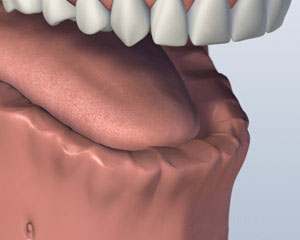

虽然很多患者都没有戴上假牙的问题, 有些人觉得很难穿,用较低的假牙吃. 一些 种植体支持的替代选项 可如果你缺少你所有的下牙.

您是否丢失了所有你的下牙?

1. 之前